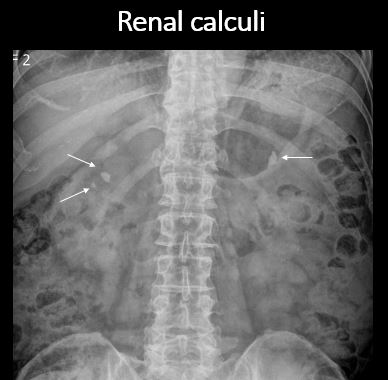

There are renal associated calcifications. |

No | NA |

There is a right or left ureteral calcification/stone anywhere from the renal pelvis to the UVJ. |